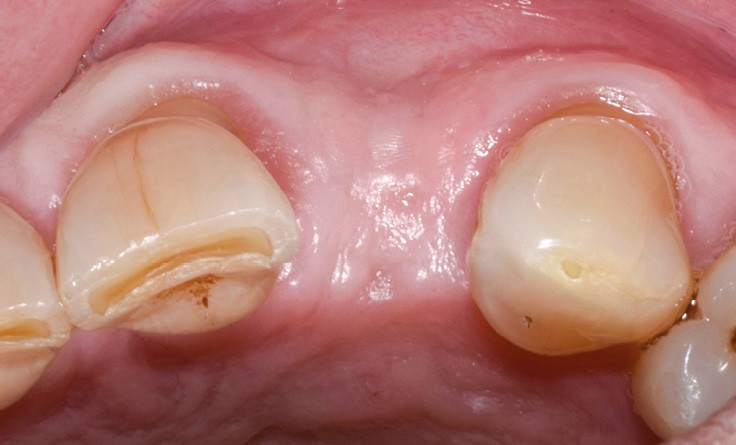

Un patient de 62 ans se présente en consultation afin de réaliser les coiffes prothétiques des dents 12 et 22. La 12 présente une restauration par prothèse transitoire non adaptée. Un implant au niveau de la 22 a été posé par un autre praticien selon une technique chirurgicale en deux temps. Le praticien a adressé le patient pour la réalisation prothétique. L’option de bridge collé cantilever mono ailette n’avait pas été retenue ou proposée selon une technique chirurgicale en deux temps. Le patient souhaite rétablir l’esthétique et la fonction de ces deux dents uniquement.

Au vu des conditions initiales, il nous apparaît impossible de restaurer une esthétique satisfaisante, notamment au niveau de l’alignement des collets, sans une chirurgie muco-gingivale associée à une réhabilitation des dents antérieures par facettes. En effet, la perte de la 22, associée à une forme triangulaire des dents, a provoqué un non-alignement des collets ainsi que la présence de trous noirs entre les dents 21-22 et 22-23. Cependant, les contraintes exprimées par le patient contre-indiquaient ce traitement.